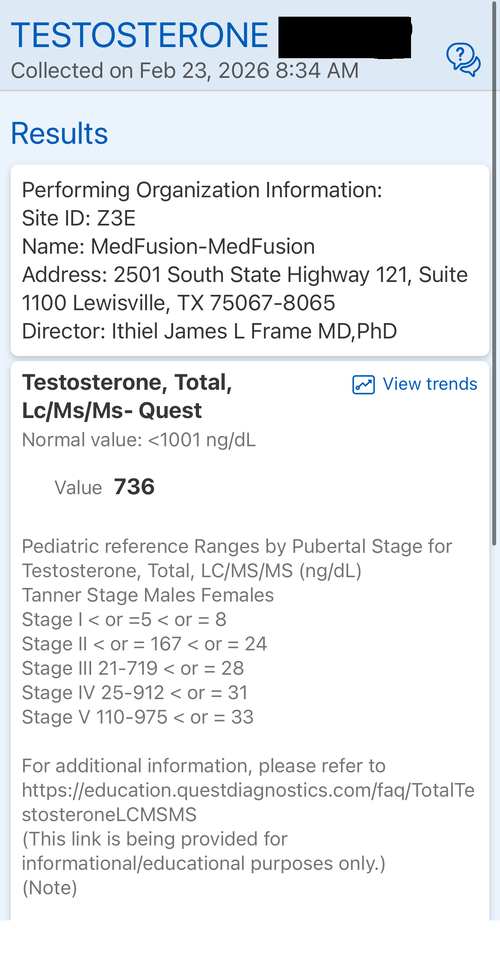

Tanner Stage: END OF STAGE 4

Introduction: The goal of this protocol is to hit my genetic potential. This is my first time experimenting with any pharmaceuticals. I am considering this based on my genetic potential allowing for more growth and the fact I need to take quick action if I want to hit my genetic target before my growth plates fuse. I may use an aromatase inhibitor but considering the fact my prior experience with pharmaceuticals is none I am fearful of having a “stack” of drugs and not having the resources to operate it well. I want to gain significant height in the most simple and low risk way possible. I will attach some blood work on my IGF-1, Cortisol, Testosterone and I have a bone age X-Ray which indicates my plates are open but estrogen exposure is starting the closure process. I will also attach a growth chart.

Tanner Stage: END OF STAGE 4

Introduction: The goal of this protocol is to hit my genetic potential. This is my first time experimenting with any pharmaceuticals. I am considering this based on my genetic potential allowing for more growth and the fact I need to take quick action if I want to hit my genetic target before my growth plates fuse. I may use an aromatase inhibitor but considering the fact my prior experience with pharmaceuticals is none I am fearful of having a “stack” of drugs and not having the resources to operate it well. I want to gain significant height in the most simple and low risk way possible. I will attach some blood work on my IGF-1, Cortisol, Testosterone and I have a bone age X-Ray which indicates my plates are open but estrogen exposure is starting the closure process. I will also attach a growth chart.